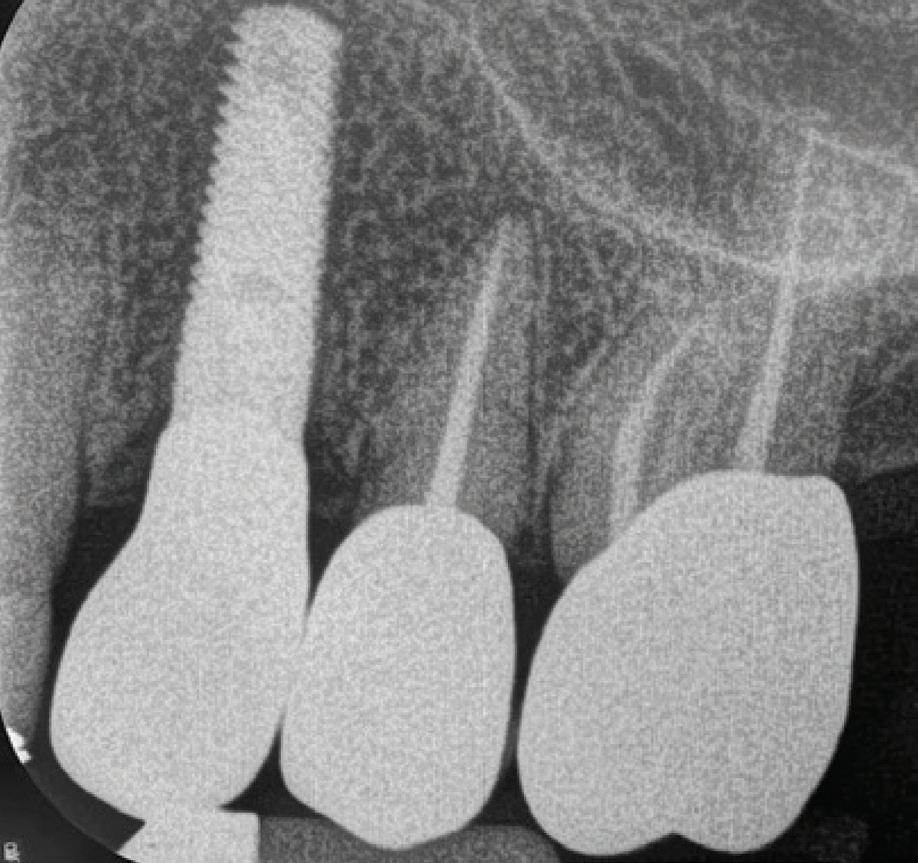

n Evaluating the digital workflow in implant dentistry: practical benefits versus technological novelty.

n Risk assessment (SAC), and the influence of implant type, material, surface characteristics and implant/abutment connections.

n Guidelines for implant planning, key parameters and management of peri-implant tissues.

n Immediate, early and late implant placement strategies.

n One-stage versus two-stage implant surgery techniques.